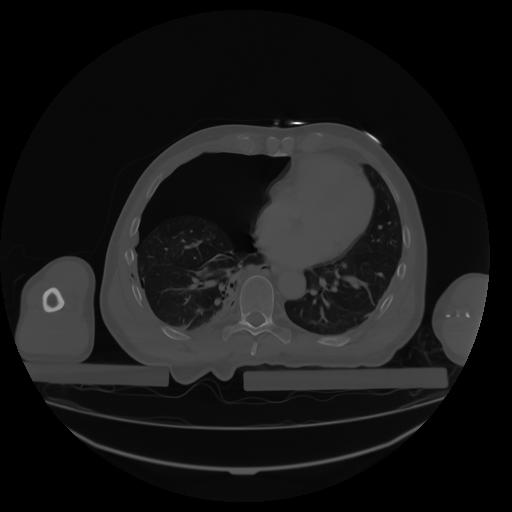

27 CUERPO,CE,Axial,3.0,CUERPO,,